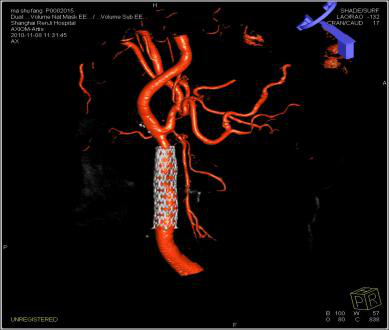

DynaCT双容积成像可以对不同容积影像如支架、弹簧圈、血管等同时显示,指导医生对支架释放、治疗预后进行评估。

血管,介入材料,骨骼的双容积成像,分辨三维空间中的位置关系,以及动静脉双血管的融合。